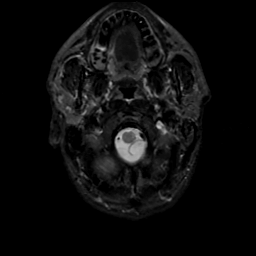

MR Study #16, June 23, 1991 -- Slice #2

[Home][Help][Clinical][Tour 1][Tour 2] Slice 2